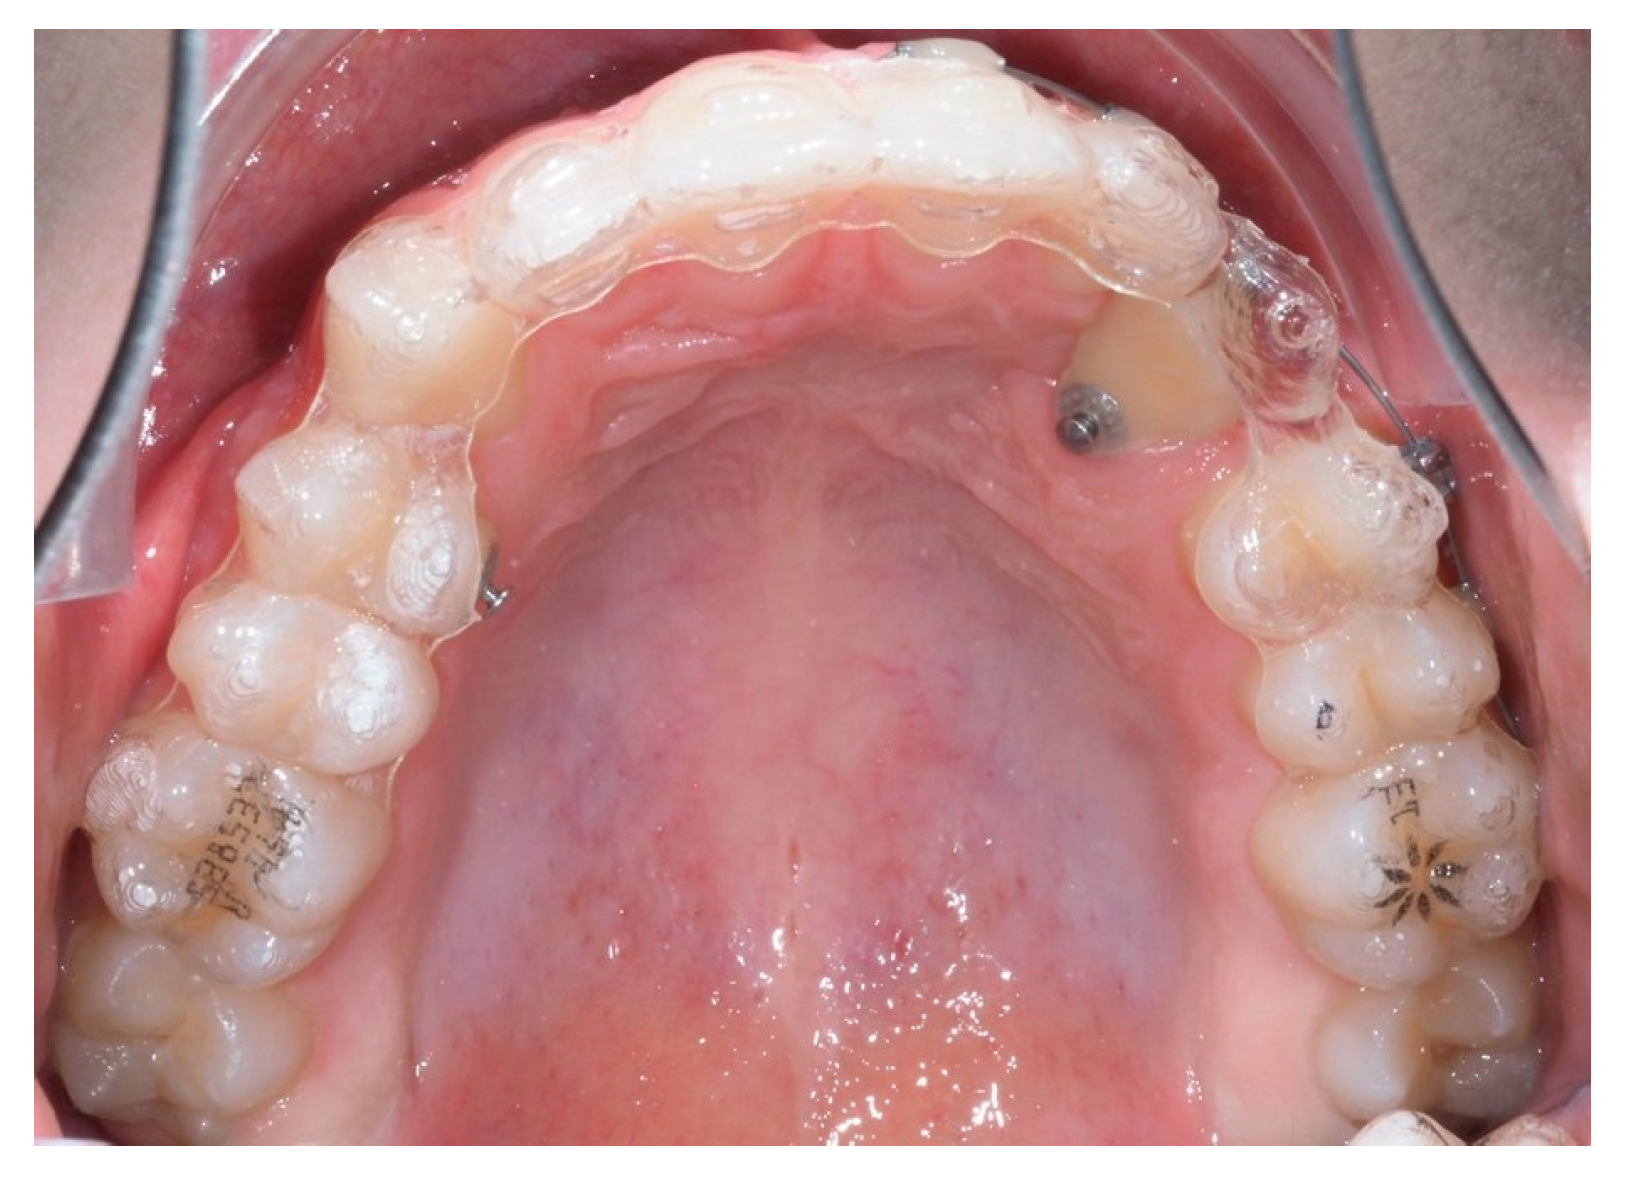

As traction progressed, the sectional appliance was extended to tooth 21 (Figure 19). A palatal button was bonded on tooth 23 to facilitate cross elastic application for vestibular movement (Figure 20). At 20 months, the bracket on tooth 23 was progressively repositioned more cervically and mesially to aid extrusion and derotation (Figure 21). A button was bonded on tooth 22 to support a wire for additional vertical anchorage. Cross elastics were also used between the palatal side of tooth 23 and buttons on teeth 33 and 34, while another elastic connected tooth 22 to 33 (Figure 22).

Figure 19.

Extension of the sectional fixed appliance up to tooth 21, with an additional tube placed on this tooth; 18 months of treatment.

Figure 20.

Palatal button on tooth 23 for cross elastic to assist in its vestibularization; 18 months of treatment.

Figure 21.

Progressive repositioning of the bracket to aid in extrusion and derotation of the canine; 20 months of treatment.

Figure 22.

Final adjustments with a button on tooth 22 for vertical recovery and cross elastics for stabilization; 24 months of treatment.

Ultimately, after 30 months of treatment, canine 23 was successfully repositioned into the dental arch, achieving functional occlusion (Figure 23).

Figure 23.

Canine 23 properly positioned in the arch in occlusion; 30 months of treatment.